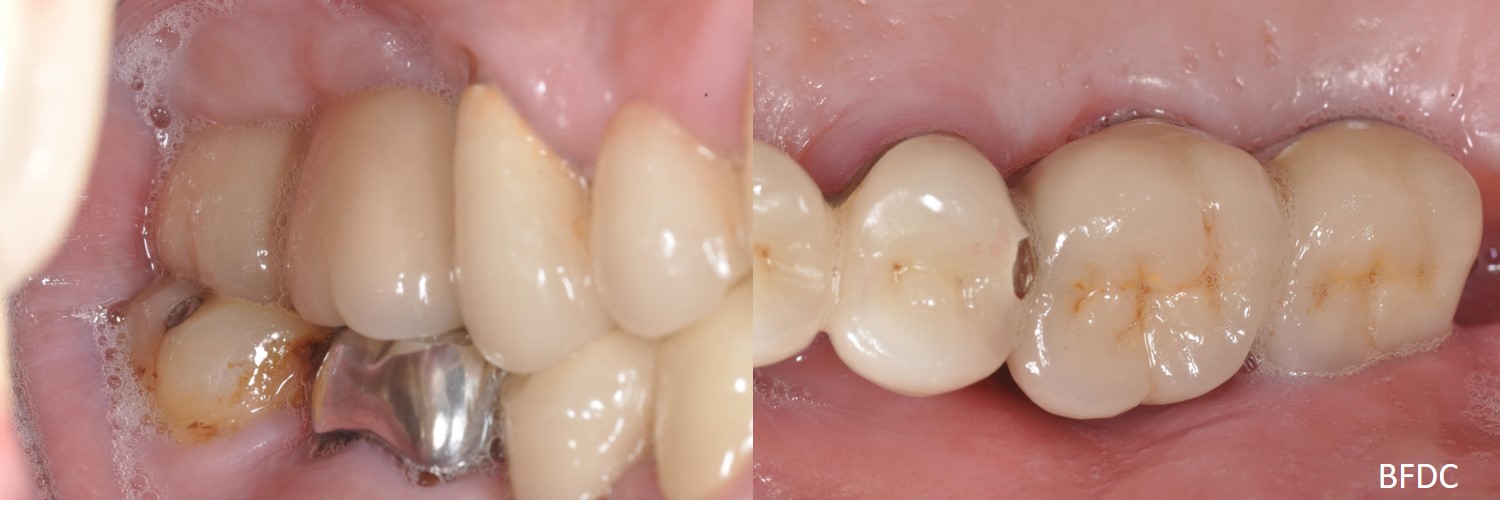

5年前,植牙剛完成

術前、術後比較